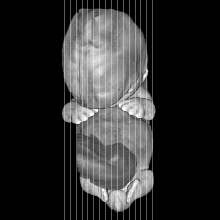

MRI Slice Selector

Mouse: click on a line below to select a view

Finger: tap a line below with a very light touch